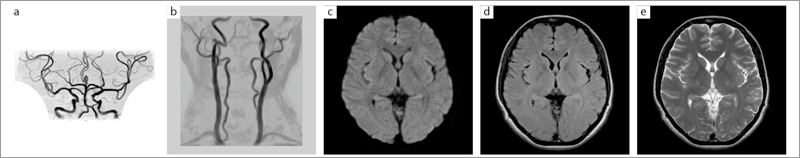

■症例1:16ch RAPID Head attachment NVコイルを使用したMRI/MRA(正常例)

a:頭部MRA,3D TOF,TR/TE/FA:23/6.9/20°,マトリックス:320×192,FOV:200mm,スライス厚:1.2mm(0.6mm),撮像時間:3分13秒

b:頸部MRA,3D TOF,TR/TE/FA:20/6.9/30°,マトリックス:256×160,FOV:230mm,スライス厚:2.0mm(1.0mm),撮像時間:3分17秒

c:DWI,DWI-EPI,TR/TE:3300/87,マトリックス:136×192,FOV:230mm,スライス厚:5mm,撮像時間:56秒

d:FLAIR,FIR,TR/TE:10000/94.4,マトリックス:256×224,FOV:230mm,スライス厚:5mm,撮像時間:2分40秒

e:T2WI,FSE,TR/TE:4500/104.0,マトリックス:288×256,FOV,230mm,スライス厚:5mm,撮像時間:1分35秒